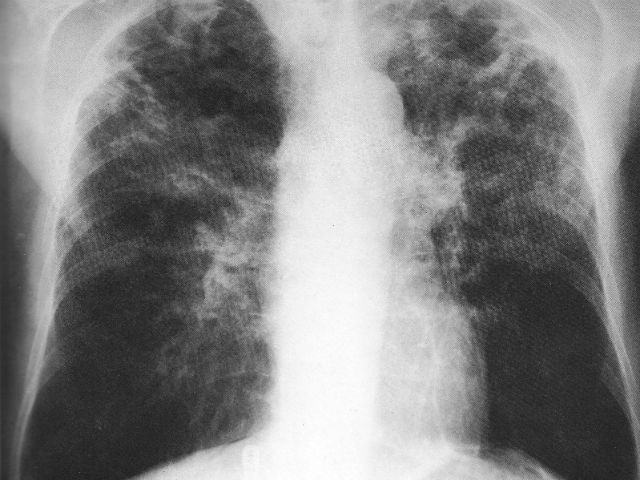

(ASCA) – ROMA – ”La tubercolosi assume nuove forme e diventa sempre piu’ difficile da combattere. Una persona su tre e’ infetta,